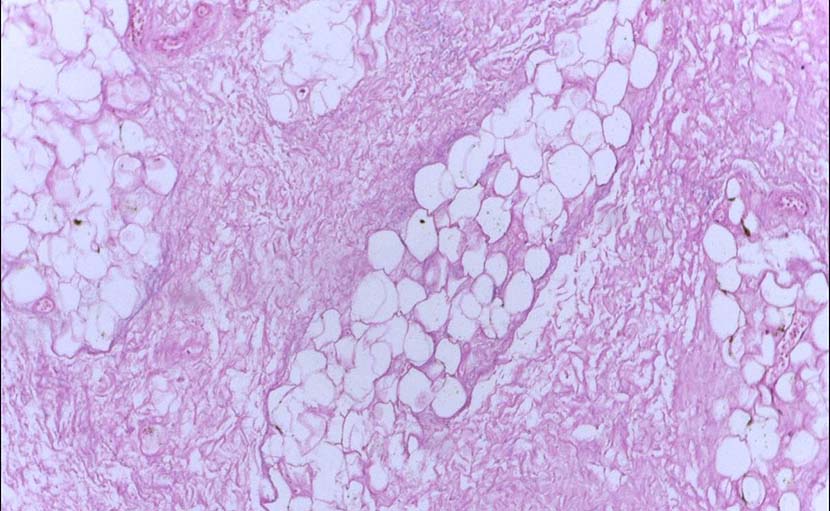

মেয়েদের স্তনে চাকা হওয়ার ৭টি কারণ ও ডাক্তারি পরামর্শ জানেন কি?

0 SHARES Share Tweet মেয়েদের স্তনে চাকা বা ব্রেস্টে চাকা অনুভুত হওয়া মেয়েদের জন্য একটি বড় শঙ্কার বিষয়। তবে ব্রেস্ট লাম্...